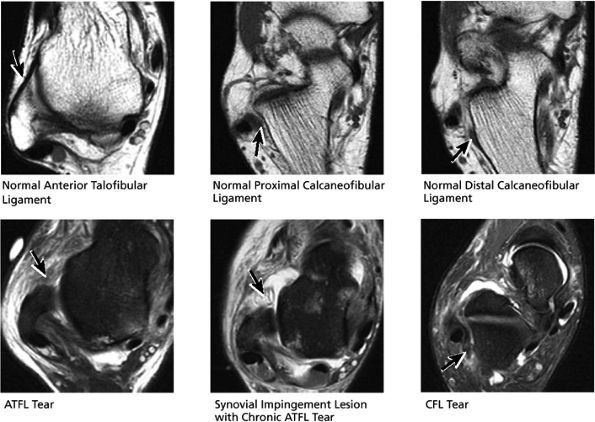

![]() |

FIGURE 5.34 Lateral Ligaments.

this image (or possibly one image posterior). On the next one or two posterior images the course of the CFL can be followed from the distal lateral malleolus posteroinferiorly to its insertion on the lateral calcaneus. On the three or four images anterior to the slice through the middle of the lateral malleolus, the full course of the ATFL is seen as a dark bundle of fibers moving directly anteriorly to insert on the lateral aspect of the talus. The lateral ligaments are examined in the coronal plane, and any findings are correlated with those seen in other planes.